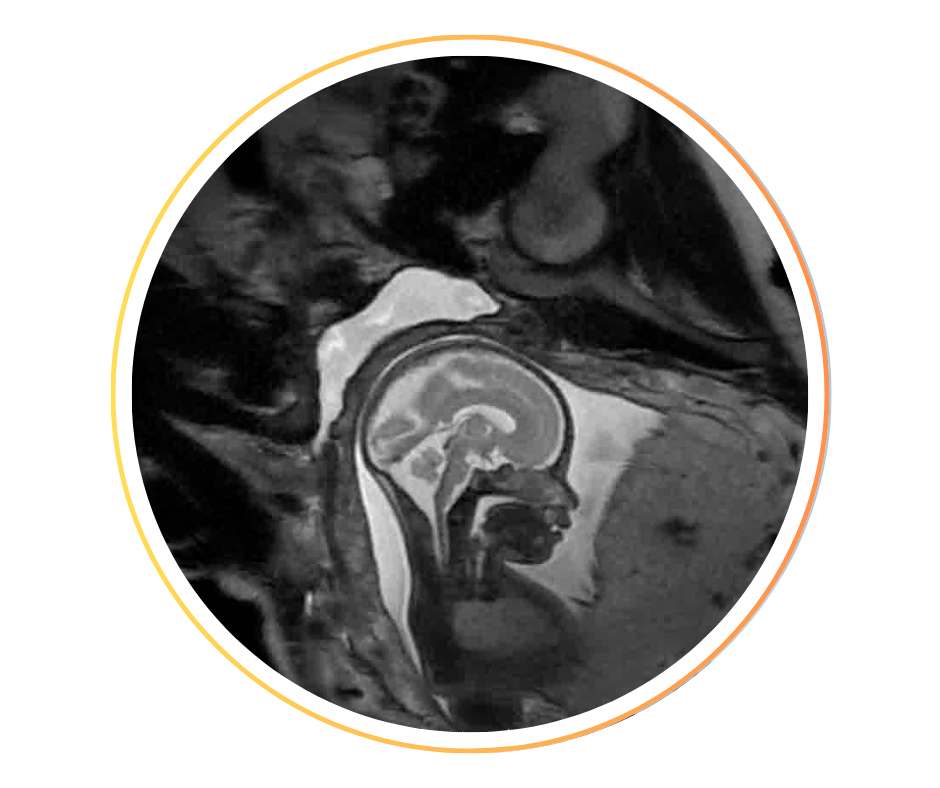

• Cerveau fœtal, développement normal et neuro-pathologies : fusion écho/IRM cerveau, perfusion cerveau ASL, tractographie, segmentation, analyse gyration.